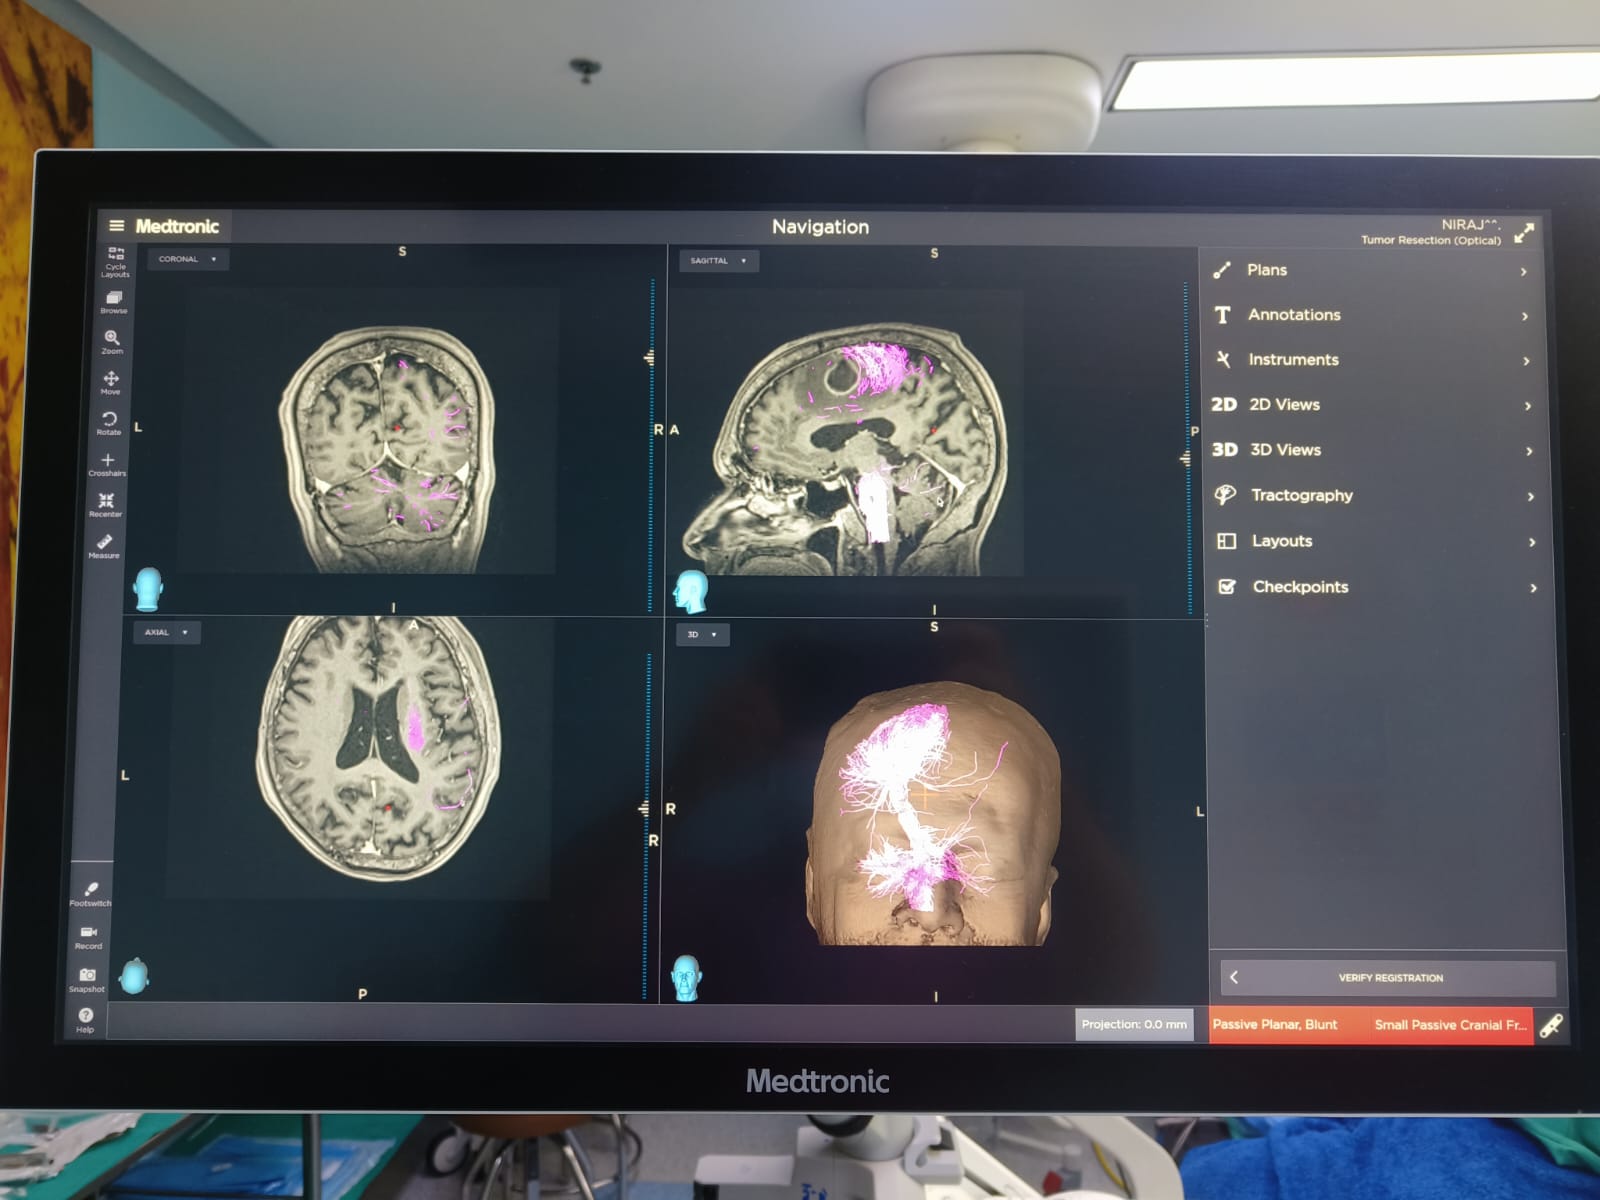

Brain Tumor Surgery